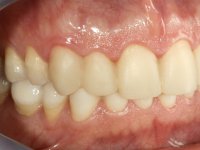

Paciente do sexo masculino, com 36 anos, não fumador. Fez tratamento ortodôntico e reabilitou esteticamente o sector anterior com restaurações em resina composta. As restaurações apresentavam um aumento vertical médio de 2 mm em relação o bordo incisal. Apresentavam-se esteticamente satisfatórias, mas com algumas fraturas incisais. O dente 1.5 apresentava um processo apical e o dente 2.6 apresentava tratamento endodôntico e uma lesão endo-periodontal. No maxilar inferior no local do dente 3.5 apresentava um implante com uma coroa aparafusada e o dente 8.5 ainda estava presente em boca com agenesia do dente 4.5. O paciente apresentava uma ligeira perda da dimensão vertical da oclusão provavelmente associada a um visível desgaste das superfícies oclusais. O periodonto era espesso e apresentava uma excelente higiene oral.

Após análise clínica e imagiológica foi proposto ao paciente recuperar a dimensão vertical da oclusão essencialmente à custa de incrementos oclusais inferiores utilizando “overlays” no sector posterior e facetas no sector anterior. A coroa aparafusada sobre o implante 3.5 seria substituída, no sentido de acompanhar este incremento. Na maxila o dente 2.6 teria extração indicada e posteriormente seria reabilitado com um implante e respetiva coroa. No sentido de reabilitar esteticamente o paciente duma forma minimamente invasiva, foi proposta a colocação de facetas feldespáticas no sector antero-superior. O objetivo de aumentar ligeiramente a D.V.O., teria como função “proteger” eficazmente o sector antero-superior.